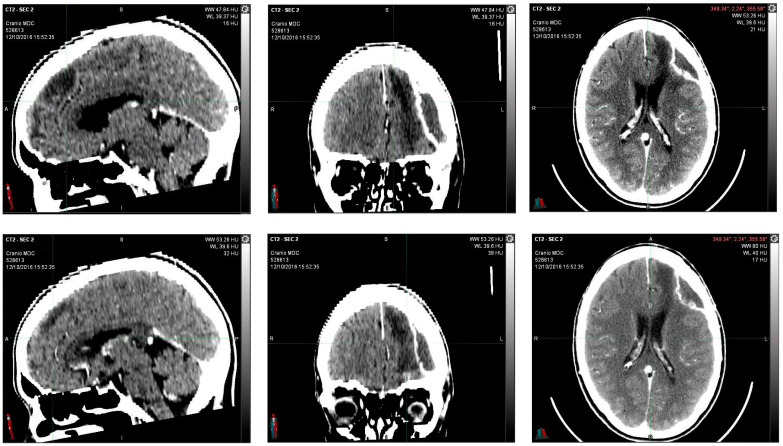

Encephalon/Cranium CT scan with contrast medium performed postoperatively on 12 October 2016 showed an apparently reduced liqueur-like collection with associated wall impregnation. Posterior to the surgical cavity, there is an approximately 2 cm hyperdense solid nodule characterized by contrast-enhancing impregnation (Figure 2).